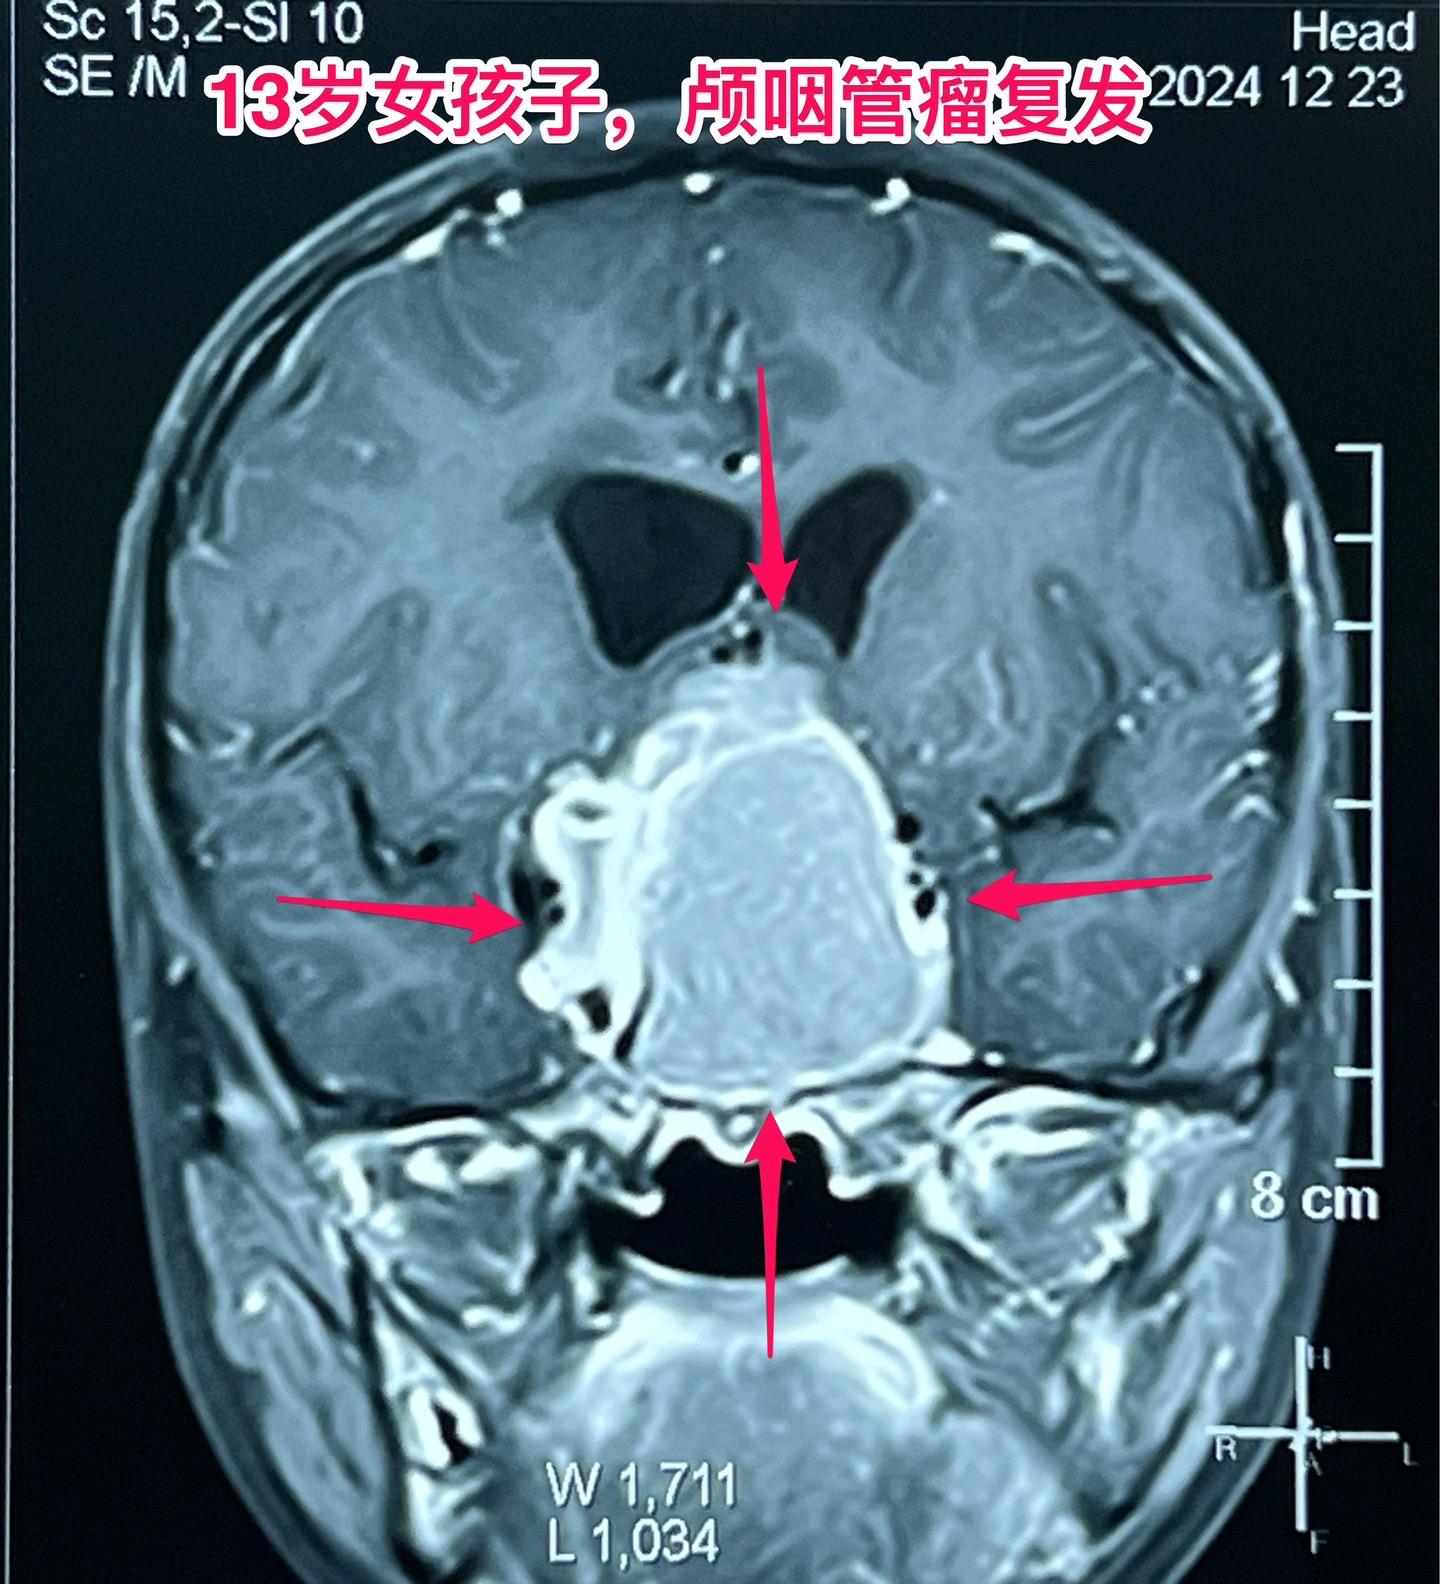

颅咽管瘤两次复发,右眼失明、左眼快失明了。13岁女孩子,因颅咽管瘤之前做过两次开颅手术。肿瘤又复发了,体积很大,垂体窝显著扩大,见图。 12月27日作了手术,将肿瘤完全切除。 这是第三次手术,手术前家长很担心左眼仅有的光感视力会不会变成全盲?会不会出现脑脊液鼻漏? 手术后患者很快就清醒了,左眼视力保住了,也没有脑脊液鼻漏出现。希望肿瘤不再复发。